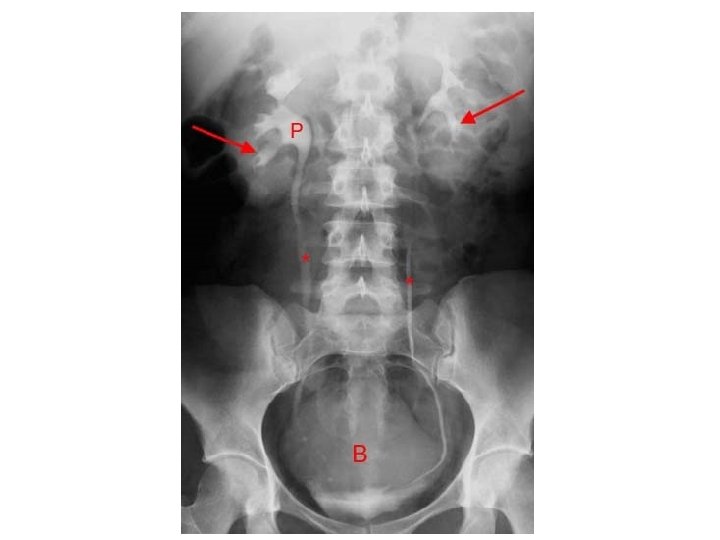

Conventional radiography • First imaging modality. • Cheap. • Useful for radioopaque stones.

Conventional radiography Image features: • Projectional image. • Image contrast determined by tissue density. • Good evaluation radio-opaque stones.

Case (1) • Young male patient presenting with left flank pain and hematuria, no fever and normal WBC count.